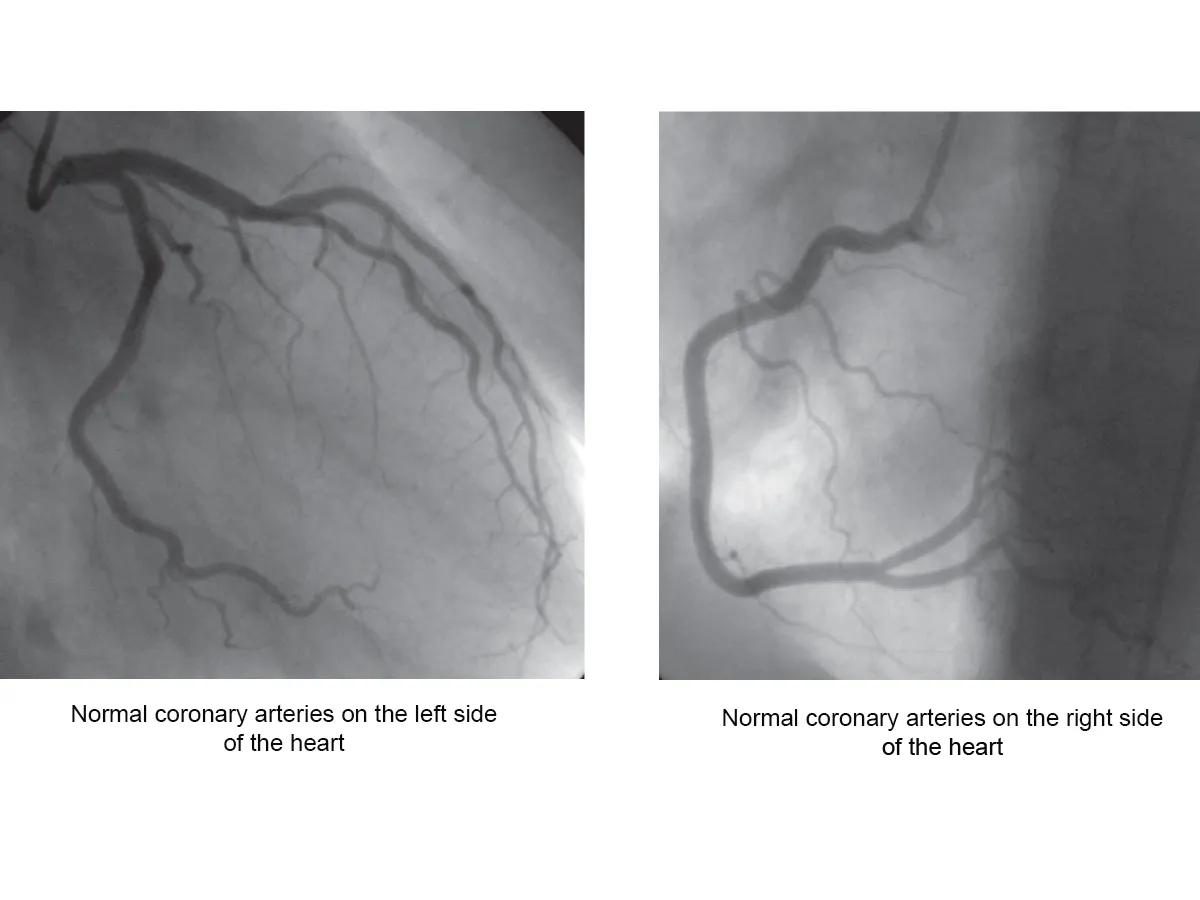

A coronary angiogram is an X-ray of the arteries in the heart. This shows the extent and severity of any heart disease, and can help you to figure out how well your heart is working.

The dye makes the blood flowing inside the blood vessels visible on an X-ray and shows any narrowed or blocked area in the blood vessel. The dye is later eliminated from your body through your kidneys and your urine.